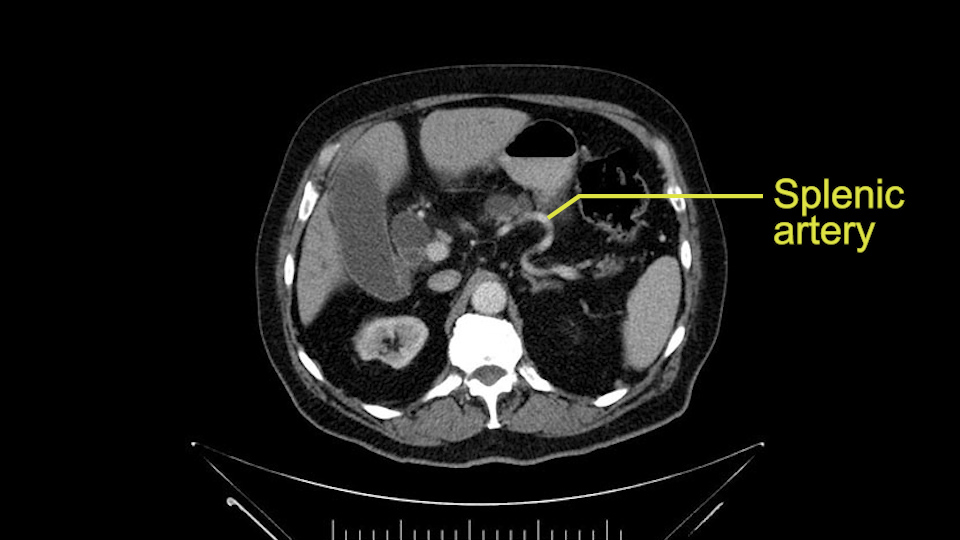

The next item that I would look at: the issue would be the vessels and usually start at the portal vein, watch the portal vein, follow it down, down-down-down to the neck of the pancreas - which is here - and there’s no impingement by tumor, which is great. The SMV and the splenic vein, which is here. The splenic vein junction is normal, which is great.

Then you look for anomalies. The one you worry about the most doing a Whipple is a replaced or aberrant right hepatic artery coming off the SMA at its origin. So again, find the SMA. You can find it because the renal vein goes through it. Follow it up, up-up-up. Nothing coming off of there that I can see here. Nothing coming off of it, nothing coming off of it and just to confirm it, look at the celiac trfurcation. There’s the celiac, there’s the bifurcation, there's the splenic artery, hepatic artery. Make sure there’s a right, which there is here. The right usually goes under the bile duct: important when you’re going around the bile duct to do a Whipple. A replaced right goes under the portal vein and the bile duct way over here on the right. That’s about it.